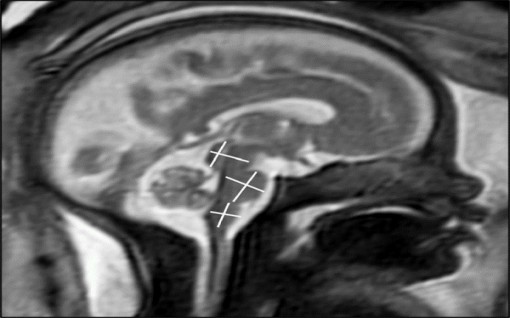

Mắc COVID-19 trong thai kỳ có gây hại cho não của thai nhi không?

Theo nghiên cứu được trình bày hôm 30/11 tại cuộc họp thường niên của Hội nghị Điện Quang Bắc Mỹ (RSNA), mắc COVID-19 ở mức độ nhẹ đến trung bình trong thời kỳ mang thai không ảnh hưởng đến não của thai nhi đang phát triển.